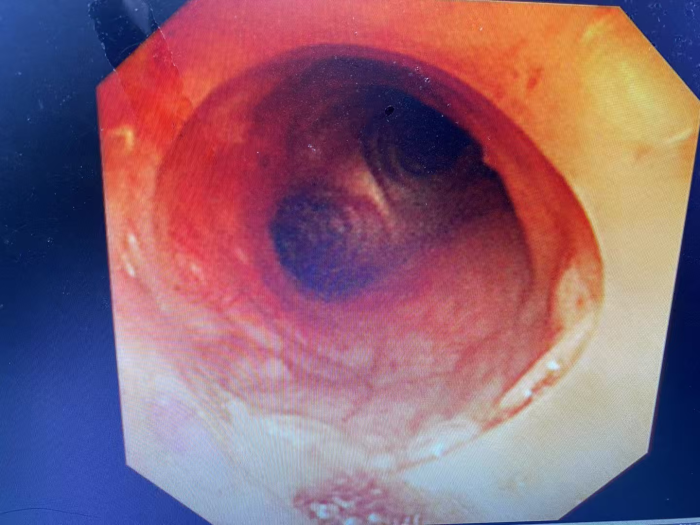

同样呼吸困难的情况也发生在54岁的黄先生身上,黄先生因食管癌晚期,在外院经多次放疗和化疗后疾病仍进展,春节期间突发明显呼吸困难至当地医院就诊,当地医院完善肺部CT后发现黄先生的食管肿瘤已严重压迫气管,气道呈现“一线天”改变,最狭窄处仅剩余5mm不到。

看着黄先生痛苦不已,家属心急如焚,打听到自治区南溪山医院院呼吸与危重症医学科二病区有神奇的呼吸介入手术可缓解呼吸困难,遂于春节期间紧急转至该病区。屈东明博士查看资料后迅速组织完善术前检查,呼吸介入团队联合麻醉科、内镜中心联合制定个性化方案。在全麻下行沙漏型硅酮支架植入术,术中发现患者情况更为严重,因肿瘤侵犯气管扭曲,鞘管无法通过最狭窄部位,同时支架推送器也无法通过鞘管。呼吸介入团队经过商量后迅速调整手术方案,终于成功植入气道支架,患者从“命悬一线”到自由呼吸!